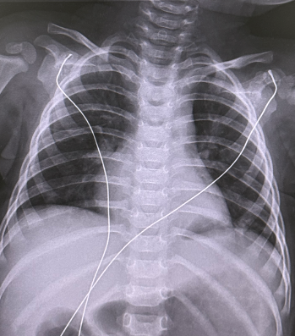

小鱼一岁时,准备接受手术,但术前的胸部增强CT结果却有些出乎意料,双侧肺内确实见到了囊性病变,但是有一支来自腹主动脉分支的异常动脉给两侧病变供血,也就是说,小鱼的病是隔离肺,而且是双侧叶内型隔离肺,这种情况极为罕见,比起叶外型隔离肺手术难度要大很多。马立霜主任带领张艳霞主治医师反复与放射科医生探讨,确认异常血供的走行、来源以及双侧隔离肺组织的位置与范围。经过科室成员的讨论,大家最终一致同意为小鱼进行胸腔镜双侧隔离肺切除术。

术前增强CT见源自腹主动脉的异常动脉分两支分别进入两侧胸腔的隔离肺